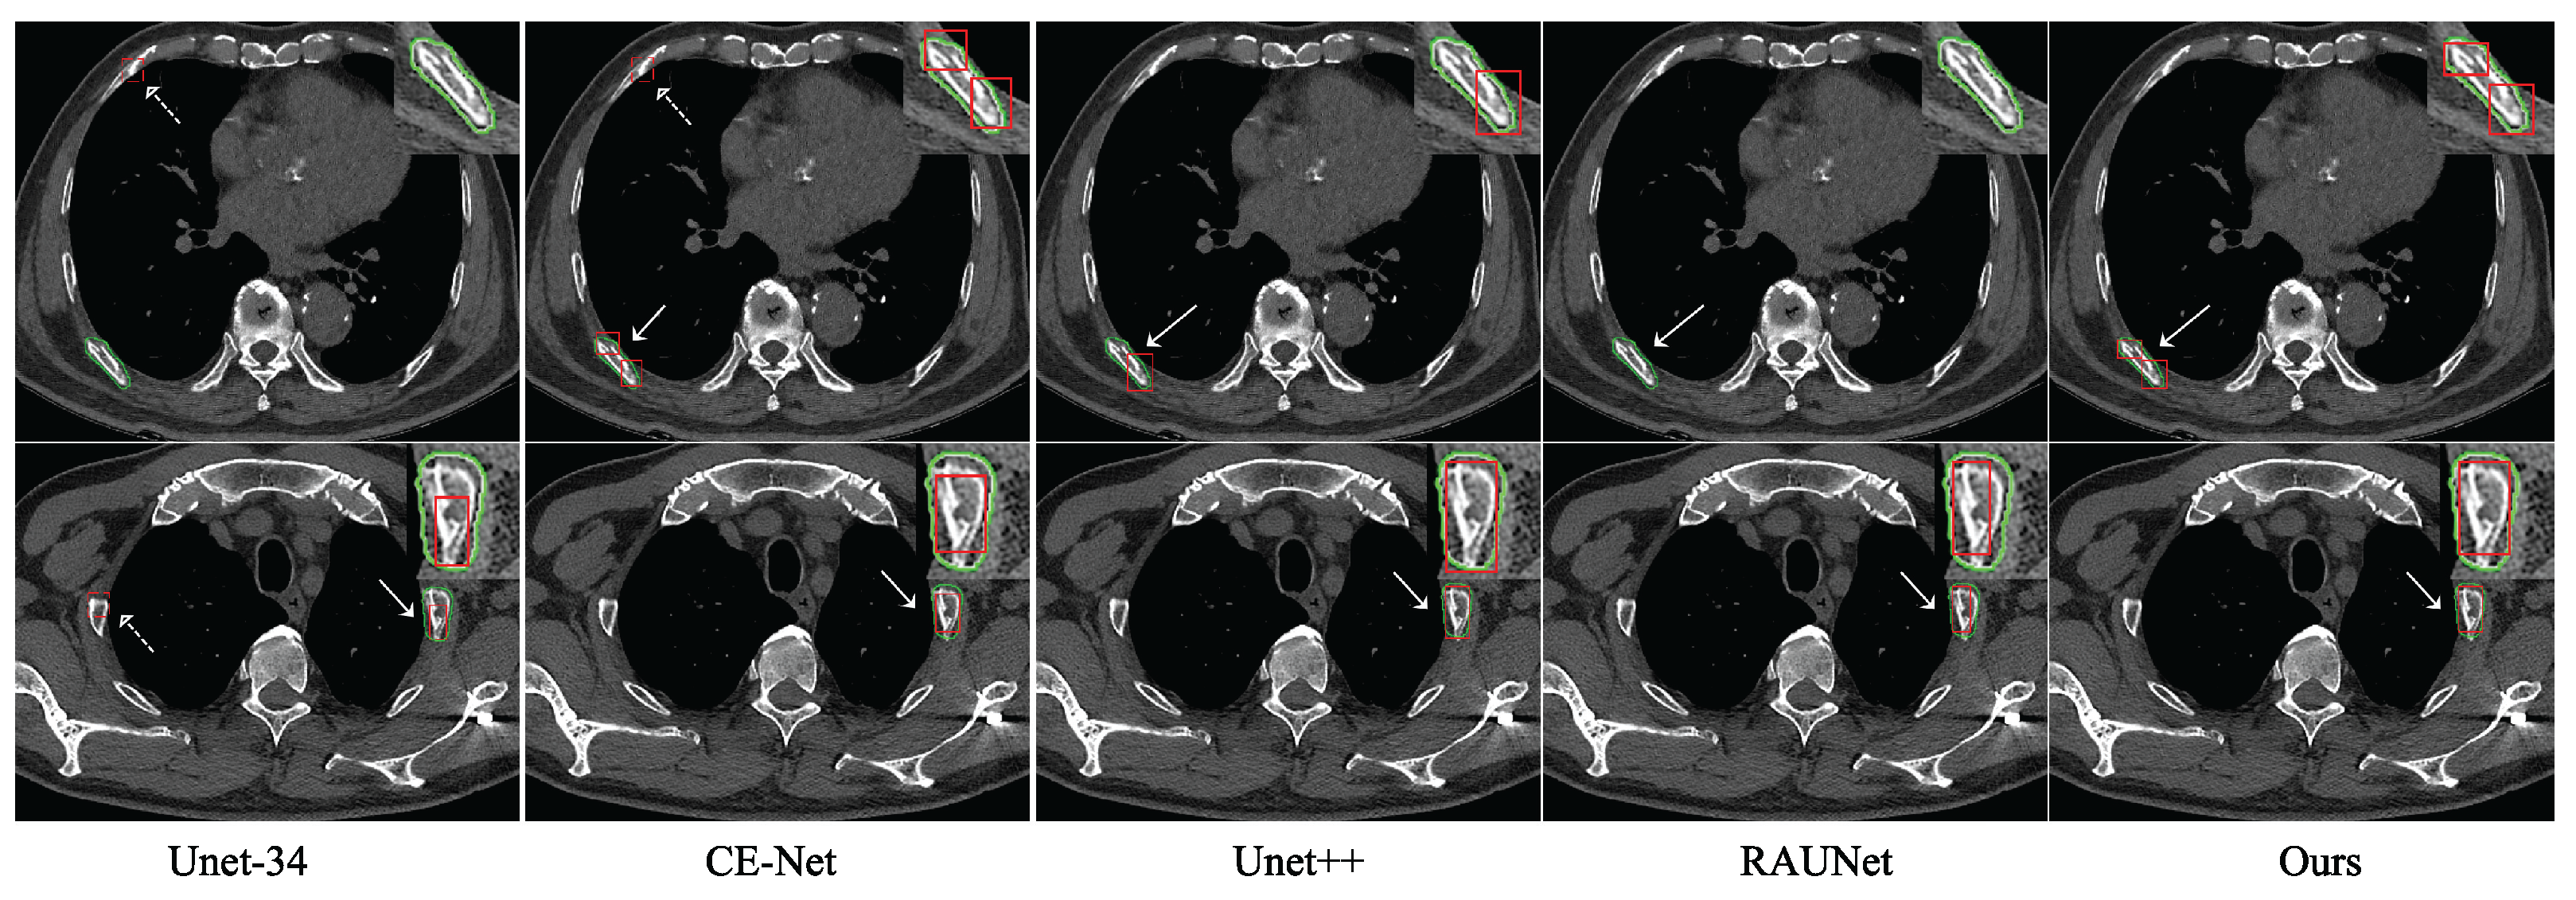

4.2.3. Comparison with Other Networks

5. Discussion